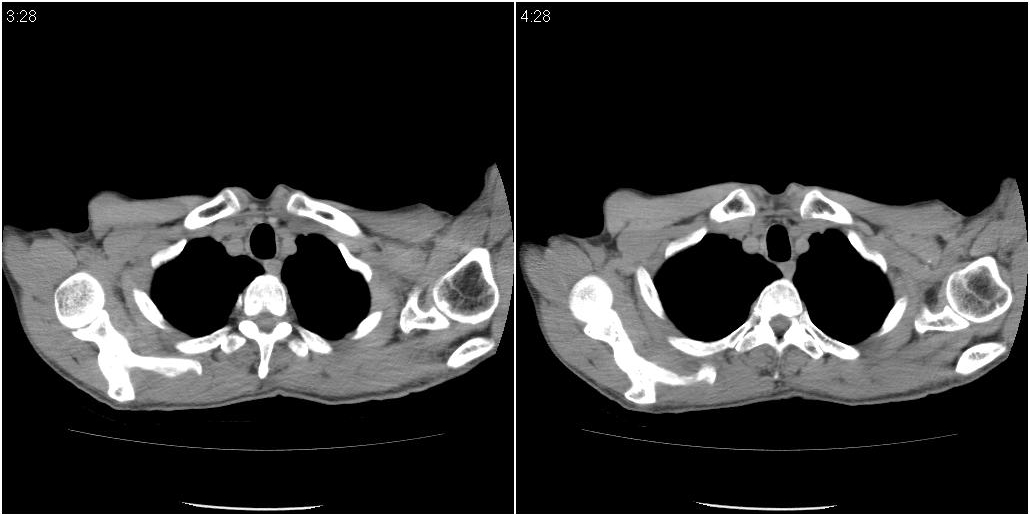

标题: ct增强:

右肺中叶阻塞性不张及肺炎,高度怀疑支气管占位,建议纤支镜检查!

考虑右肺中叶感染。左肺下叶支扩。

右中肺阻塞性炎症,建议纤支镜!双下支扩感染。

1)右肺中叶慢性炎症并支气管扩张,节段性肺不张。2)两肺下叶支气管扩张。